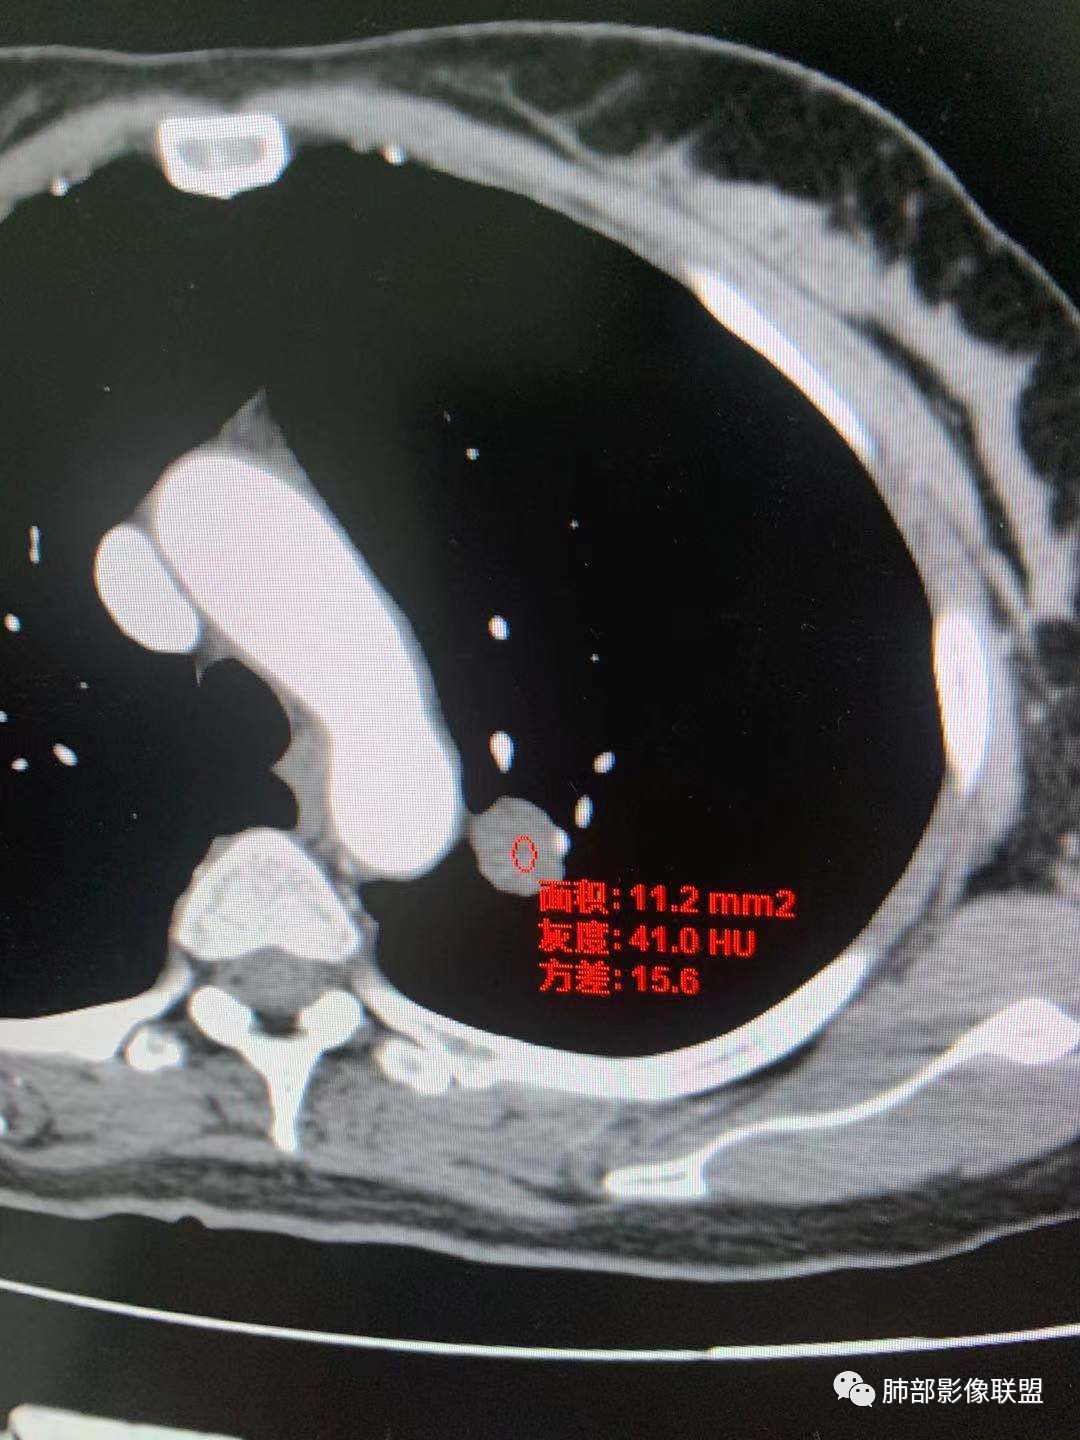

有棘状突起,强化渐进性,强化了四十左右

CT值30HU;增强后:41/76HU

强化幅度:46HU

一.尖后段高密度大结节:

1.左肺上叶尖后段较大类圆形实性密度结节影,密度均匀,中等程度强化。

2.实性密度区边缘相当清楚,表面欠光整,偶见毛刺、棘突和旁出血管结构,未见典型的深分叶及邻近胸膜凹陷。

3.可疑支气管进入受阻。可惜缺乏连贯图像或冠矢状位以资判断。

4.病灶与胸膜之间有连线,邻近段支气管及肺血管整体后移,提示病灶还是有一定收缩性。

如上,单就这实性结节,硬化性肺细胞瘤(PSP)和腺癌似乎都能够解释,形态太规整了一些。

5.病灶周围见边界清楚的磨玻璃影,有点醒目,有点意外!

这是无论如何不能忽视的征象!

这点强烈提示,要么整个病灶恶性(腺癌),要么良性病灶旁滋生恶性病灶。